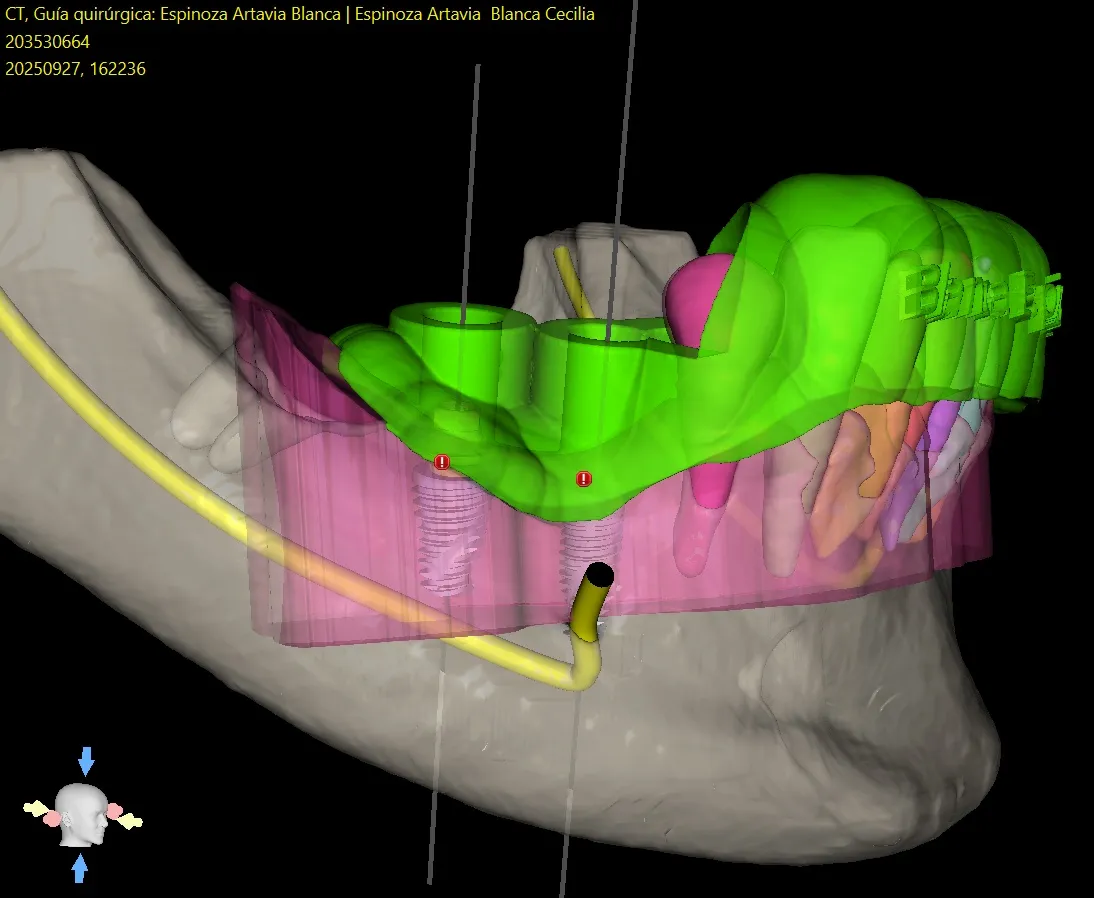

This is the most important advantage. By planning in 3D, the surgeon can "see" through the bone and gum.

- Safety: It allows for the identification and marking of vital anatomical structures (like the inferior alveolar nerve or the maxillary sinus). The surgical guide ensures the implant is placed at a safe distance from these structures, drastically reducing the risk of complications such as paresthesia (numbness of the lip) or sinusitis.

Since the surgeon knows with complete certainty where the bone is and where the implant will go, it is often not necessary to raise a large flap (cutting and separating the gum to see the bone).

- Flapless Surgery: In many cases, the surgery can be performed by making only a small circular incision (a "punch") in the gum, just the size of the implant.